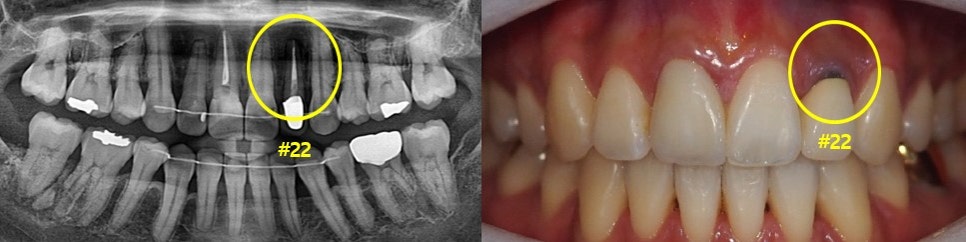

먼저 초진 구강 사진과 파노라마사진을 보도록 할게요.

먼저 파노라마 사진 속 표시된 곳을 보시면 신경치료 이후 크라운까지 씌우신 모습입니다.

두 사진으로 보시면 잇몸 쪽의 염증을 확인할 수 있습니다.

그럼 자세히 보면 뿌리 끝 쪽에 검은 공간이 보이는데 '치근 낭종' 이 있다는 것을 확인할 수 있습니다.

#22 치아는 이미 타치과에서 신경치료 + 크라운 치료가 완료된 치아였습니다.